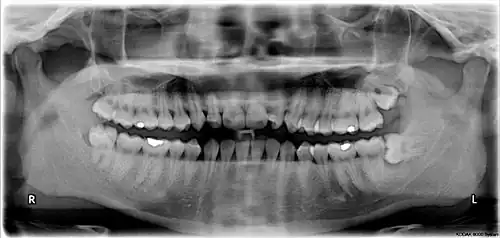

The third molar, commonly called wisdom tooth, is the most posterior of the three molars in each quadrant of the human dentition. The age at which wisdom teeth come through (erupt) is variable,[1] but this generally occurs between late teens and early twenties.[2] Most adults have four wisdom teeth, one in each of the four quadrants, but it is possible to have none, fewer, or more, in which case the extras are called supernumerary teeth. Wisdom teeth may become stuck (impacted)[3] and not erupt fully, if there is not enough space for them to come through normally. Impacted wisdom teeth are still sometimes removed for orthodontic treatment, believing that they move the other teeth and cause crowding, though this is disputed.[4][5]

Impacted wisdom teeth may suffer from tooth decay if oral hygiene becomes more difficult. Wisdom teeth that are partially erupted through the gum may also cause inflammation[3] and infection in the surrounding gum tissues, termed pericoronitis. More conservative treatments, such as operculectomies, may be appropriate for some cases. However, impacted wisdom teeth are commonly extracted to treat or prevent these problems. Some sources oppose the prophylactic removal of disease-free impacted wisdom teeth, including the National Institute for Health and Care Excellence in the UK.[4][6][7]

Wisdom teeth (often notated clinically as M3 for the third molar) have long been identified as a source of problems and continue to be the most commonly impacted teeth in the human mouth. Impaction of the wisdom teeth results in a risk of periodontal disease and dental cavities.[29] Impacted wisdom teeth lead to pathology in 12% of cases.[30]

Impacted wisdom teeth are classified by the direction and depth of impaction, the amount of available space for tooth eruption and the amount of soft tissue or bone that covers them. The classification structure allows clinicians to estimate the probabilities of impaction, infections and complications associated with wisdom teeth removal.[31] Wisdom teeth are also classified by the presence of symptoms and disease.[32]